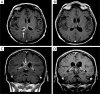

Primary central nervous system lymphoma (PCNSL) has long been associated with an inferior prognosis compared to other aggressive non-Hodgkin's lymphomas (NHLs). However, during the past 10 years an accumulation of clinical experience has demonstrated that long-term progression-free survival (PFS) can be attained in a major proportion of PCNSL patients who receive dose-intensive consolidation chemotherapy and avoid whole brain radiotherapy. One recent approach that has reproducibly demonstrated efficacy for newly diagnosed PCNSL patients is an immunochemotherapy combination regimen used during induction that consists of methotrexate, temozolomide, and rituximab followed by consolidative infusional etoposide plus high-dose cytarabine (EA), administered in first complete remission (CR). Other high-dose chemotherapy-based consolidative regimens have shown efficacy as well. Our goal in this review is to update principles of diagnosis and management as well as data regarding the molecular pathogenesis of PCNSL, information that may constitute a basis for development of more effective therapies required to make additional advances in this phenotype of aggressive NHL.